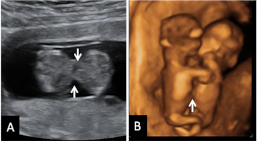

Flujo patológico en el conducto venoso

Doppler en conducto venoso. Registro normal (marcado con la letra A) y registro patológico (letra B), con onda a negativa (flechas).